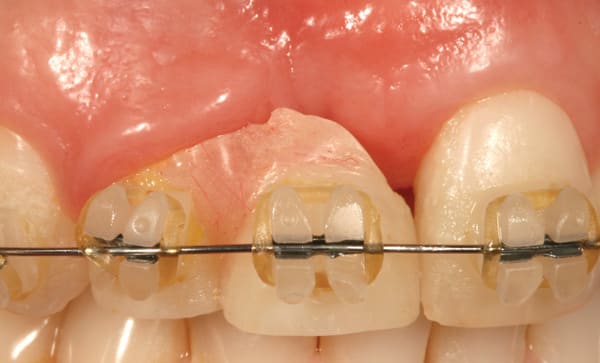

A 38-year old Caucasian female patient presented with a high smile line and loss of the papilla between tooth No. 7 and edentulous adjacent site No. 8 (Figure 1). Understandably, the patient was unhappy and embarrassed about her esthetic condition. Her dental history revealed tooth replacement of No. 8 with an implant that eventually failed. The site had been previously bone grafted upon implant removal. She was given a composite pontic No. 8 bonded to a tooth No. 7 composite veneer as a transitional restoration. The implant was positioned too close to the proximal surface of tooth No. 7, which stripped the periodontal attachment of the root and ultimately caused loss of the papilla (Figure 2). As previously outlined, the treatment sequence would be to first provide a provisional restorative solution to evaluate the projected outcomes and assess if the patient was willing to undergo orthodontic therapy. In this situation, a full-coverage crown No. 7 with a cantilevered pontic No. 8, with artificial acrylic gingiva to replace the lost papilla on the mesial aspect of tooth No. 7 was used as a transitional temporary prosthesis (Figure 3). In addition, a composite resin (Venus® Pearl, Heraeus Kulzer, https://heraeus-kulzer.com) restoration was placed on the mesial aspect of tooth No. 9 to restore its individual tooth proportion and shape. The patient’s esthetic outcome could now be evaluated with restorative correction alone; it was therefore mutually determined that the correction of her deformity would best be served with additional orthodontic forced eruption therapy. A fixed orthodontic appliance (brackets) was bonded to the teeth and temporary prosthesis. The level of the interproximal pink acrylic was used as a therapeutic guide for the amount of forced eruption required as well as the alignment of the mesial papilla of No. 7 to that of the adjacent papillae height (Figure 4). Floss was used to elevate the amount of vertical movement achieved relative to the adjacent papilla tooth No. 9. Eventually, all the artificial pink acrylic was removed. (Note that the distal papilla on tooth No. 7 also comes more incisal—in fact, it is slightly excessive at the endpoint of treatment [Figure 5]). However, the distal papilla and midfacial tissues of tooth No. 7 can be reshaped through clinical crown lengthening toward the end of treatment prior to definitive restoration, thereby restoring the proper papilla height-to-tooth ratio of 40%. After stabilization of tooth No. 7 for a minimum of 6 months post-orthodontics, an implant was placed in site No. 8. A papilla-sparing incision design was used for flap elevation (Figure 6), bone allograft (Puros® Demineralized Bone Matrix, Zimmer, www.zimmer.com) was used to further augment the facial aspect of the ridge simultaneously with implant placement (Certain® Implant System, Biomet 3i, www.biomet3i.com) (Figure 7), and a resorbable membrane (BioMendExtend, Zimmer) was used for guided bone regeneration.